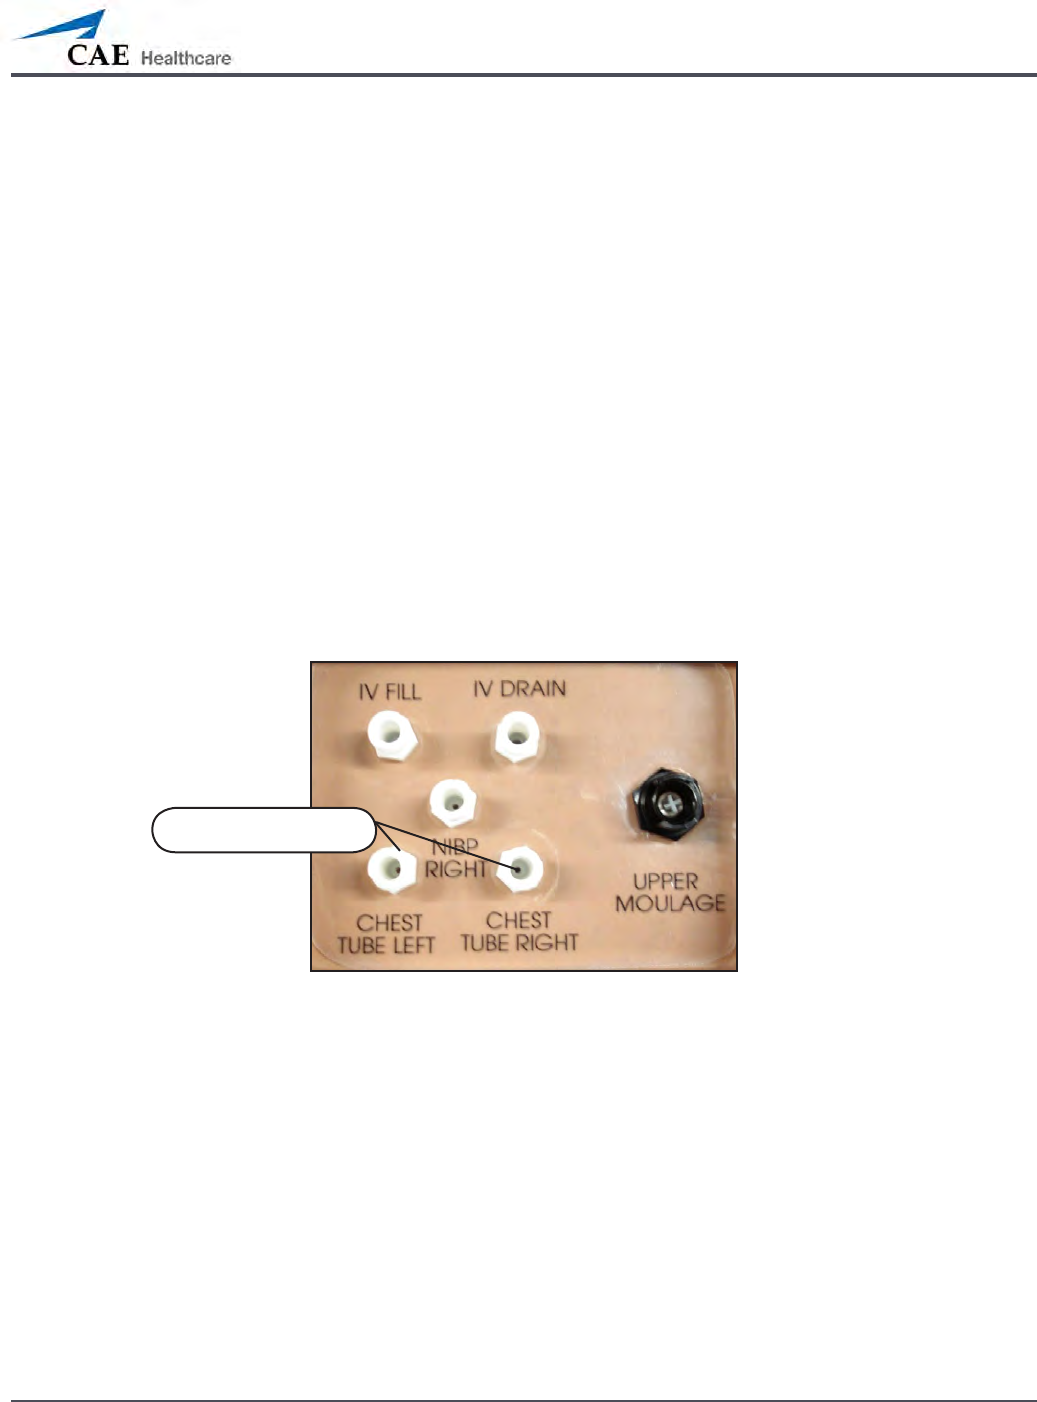

METIman’s Right Shoulder

Chest Tube ports

Connect to the simulator by attaching the end of the IV spike set tubing to 6.

METIman’s Right Shoulder

Chest Tube ports